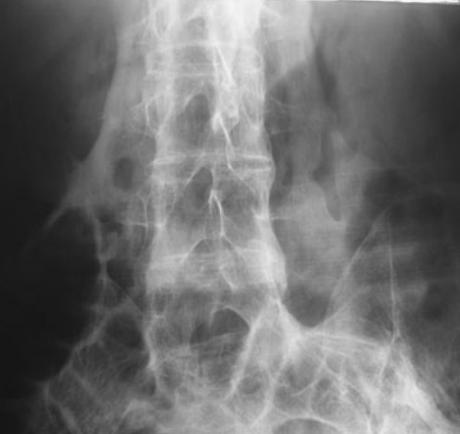

• Diagnosis is made with radiographs showing peripheral bone formation with central lucent area within soft tissues.

• Radiographs

• peripheral bone formation with central lucent area

• may appear as "dotted veil" pattern

• lesion has an eggshell appearance